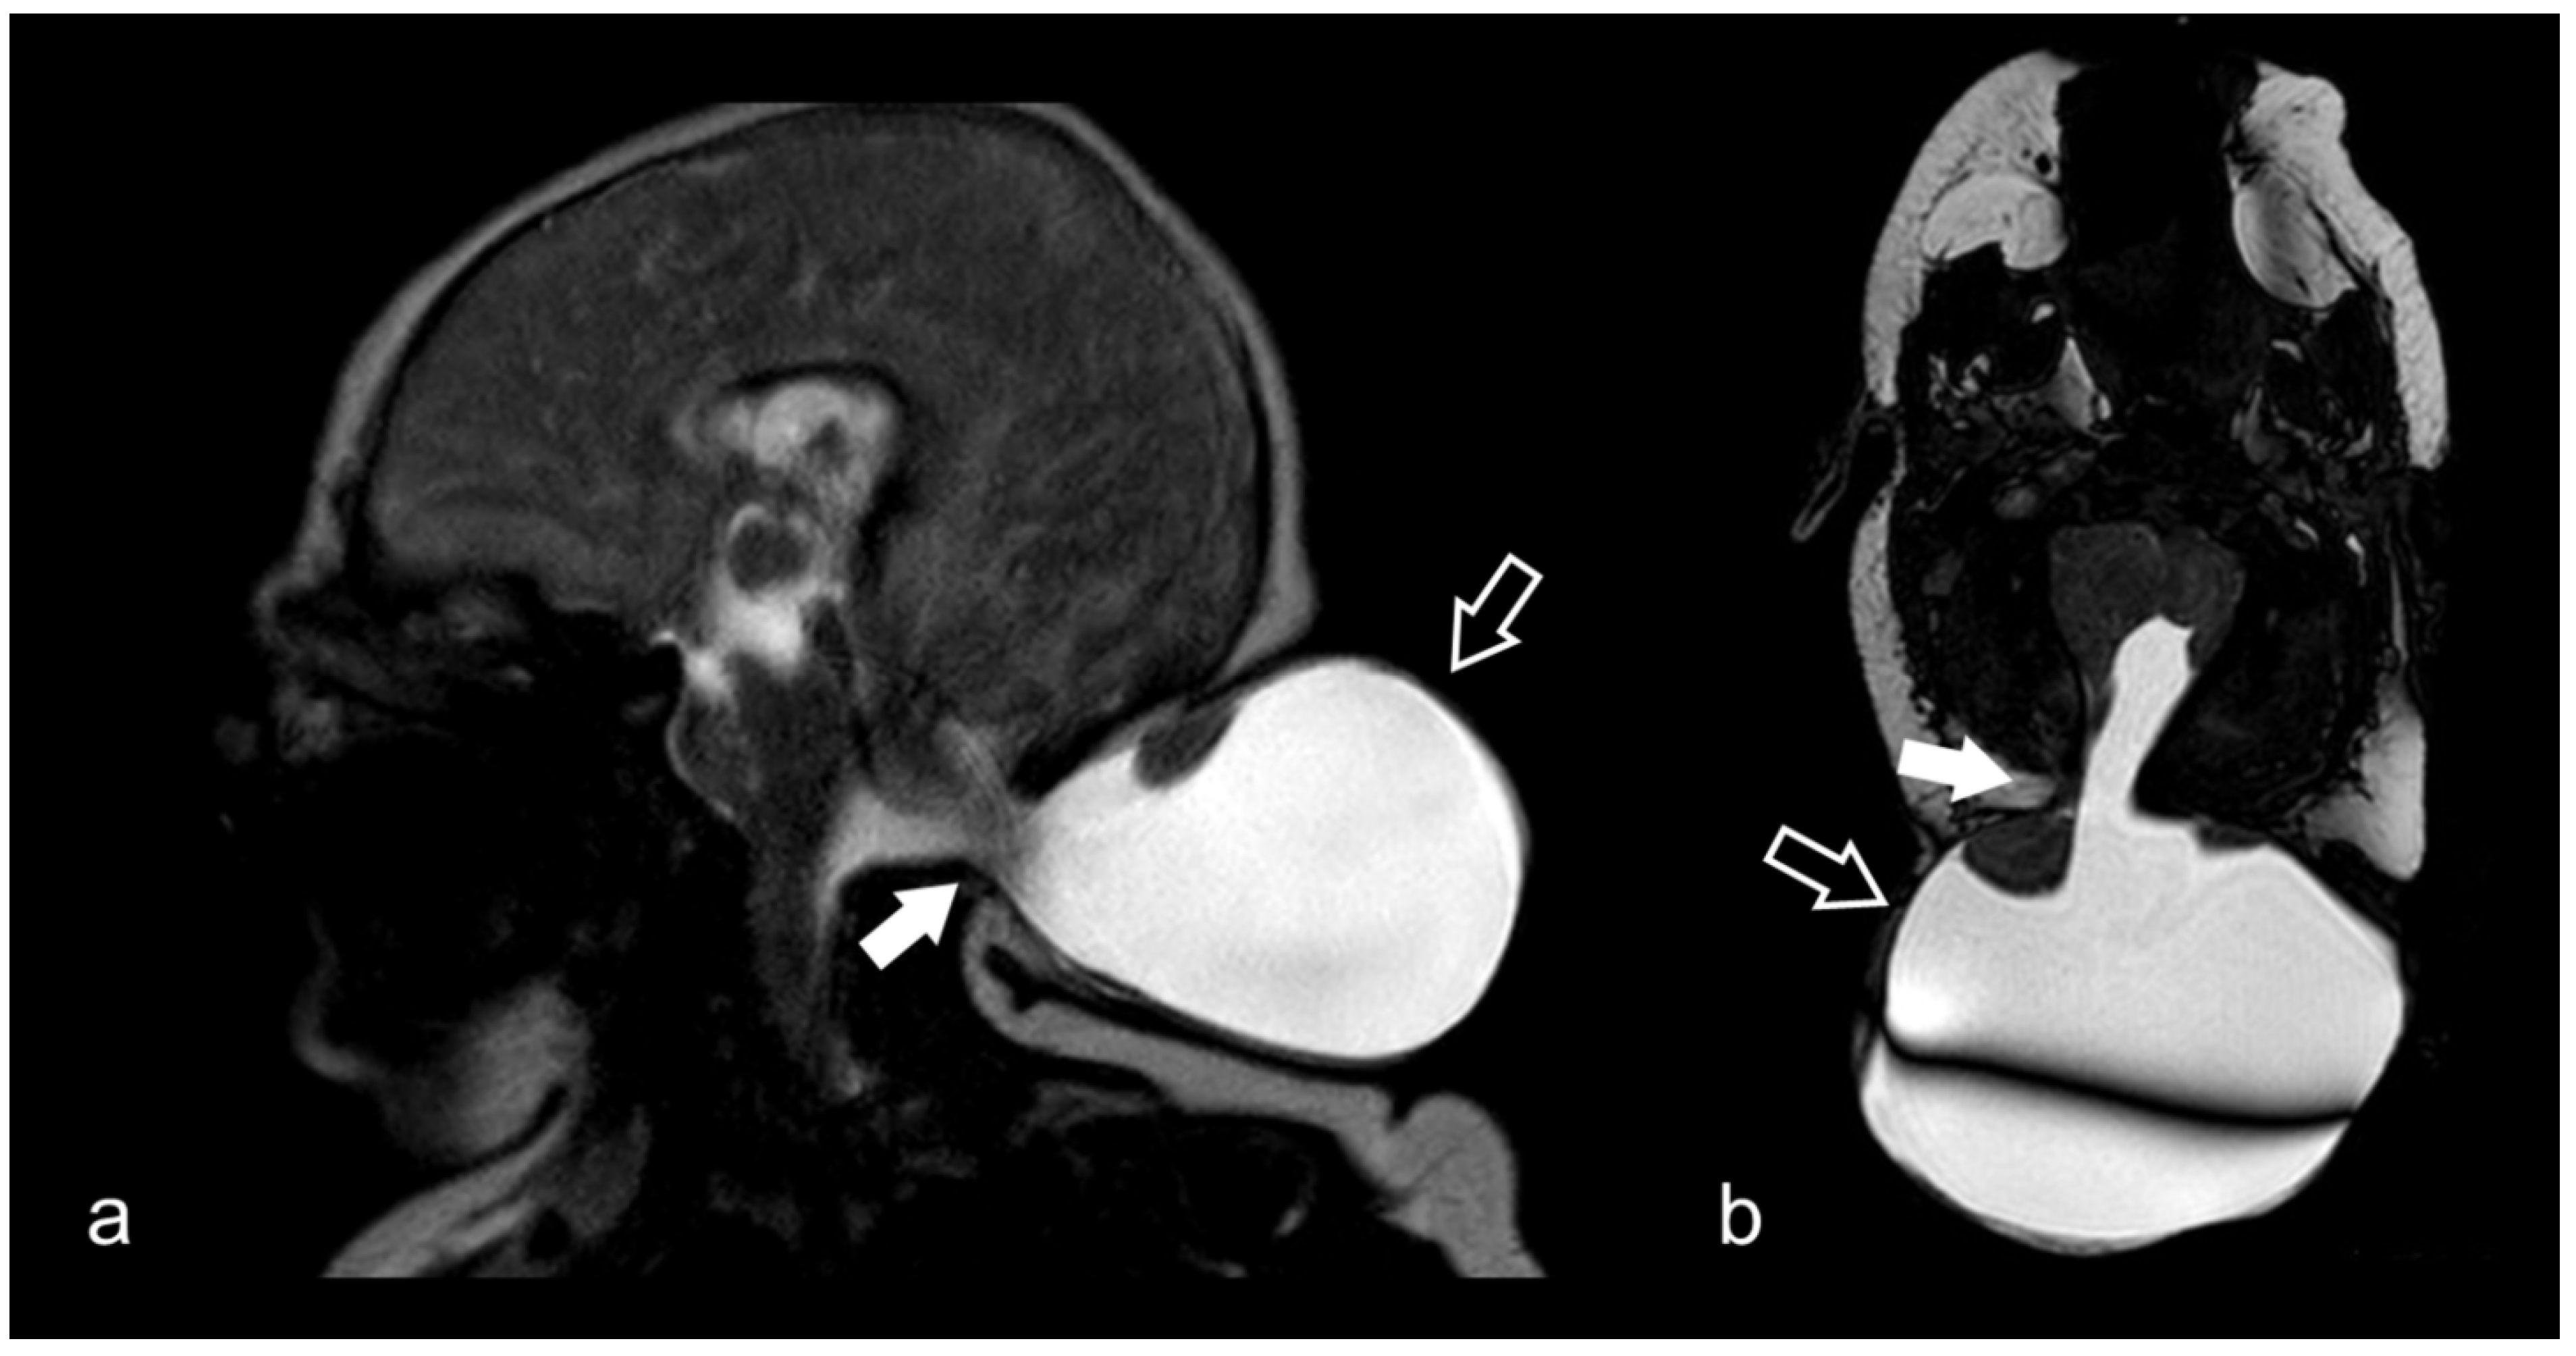

3.8. Cerebellopontine Angle Lesions

3.10. Cranio-Cervical Malformations (Chiari I)